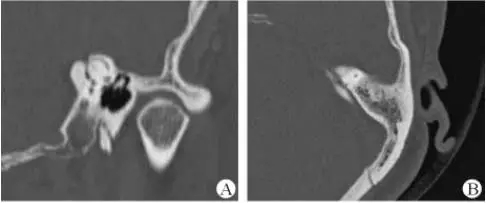

1、上半規(guī)管裂綜合征

內(nèi)耳結(jié)構(gòu)非常微妙。即使是內(nèi)耳中大頭針樣的孔洞也能造成平衡失調(diào)。患者常常不敢進(jìn)行如走路或轉(zhuǎn)頭的日常活動(dòng)。此罕見(jiàn)疾病,醫(yī)學(xué)專家預(yù)估至少影響著人口的1%。可造成惡心,眩暈以及對(duì)噪聲極高的敏感性。病人還常常抱怨他們能聽(tīng)到血管跳動(dòng)的聲音。其中一位患者曾告訴耳科專家,他都能聽(tīng)到自己轉(zhuǎn)動(dòng)眼睛的聲音。

診斷及治療

醫(yī)生若懷疑此病將會(huì)安排內(nèi)耳CT掃描。在大多數(shù)案例中,一旦此病被耳鼻喉科醫(yī)生或其它聽(tīng)力健康專家確診,則可實(shí)行手術(shù)治療。外科手術(shù)風(fēng)險(xiǎn)包含聽(tīng)力損失以及神經(jīng)損傷;重建及復(fù)原需內(nèi)耳的治療以及大腦的重塑。

2、膽脂瘤

另一個(gè)不常見(jiàn)的疾病叫膽脂瘤,發(fā)病率為1/10000,這個(gè)“腫瘤”在內(nèi)耳中逐漸生長(zhǎng)。盡管不是惡性的,但也能導(dǎo)致永久性的聽(tīng)力損失以及其它嚴(yán)重的疾病,比如腦膜炎。癥狀是有臭味的耵聹以及聽(tīng)力損失。